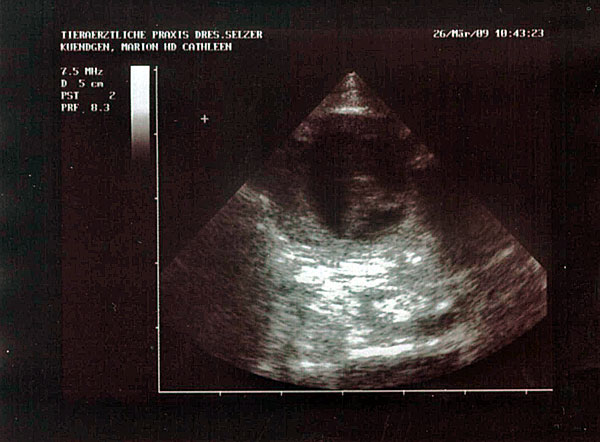

Und noch ein Fötus